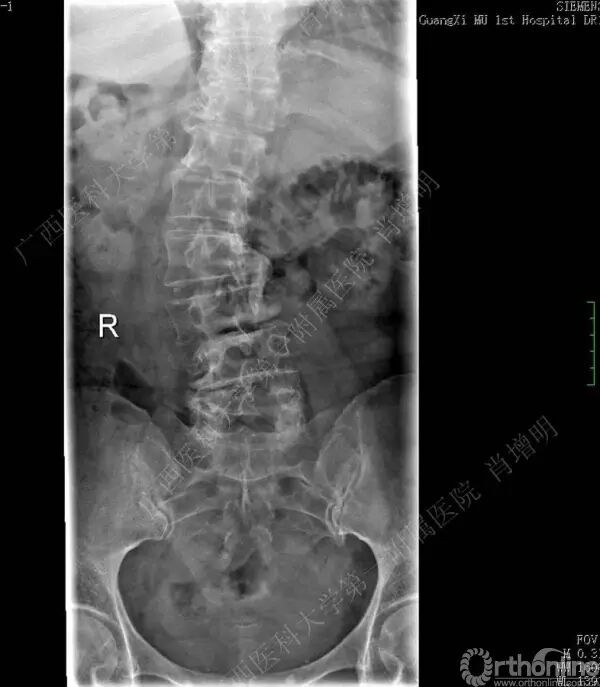

退变性脊柱侧凸是由于椎间盘退变后继发小关节退变,椎管和神经根管容积变化以及脊柱失稳,畸形等病理改变,以疼痛和神经压迫症状为主要表现的常见疾病。

退变性脊柱侧凸多发于50岁以上的中老年群体,是现代常见的老年疾病。多年来,针对该病的临床研究一直没有停步,广西医科大学第一附属医院肖增明教授细致地介绍了该病的诊疗进展。